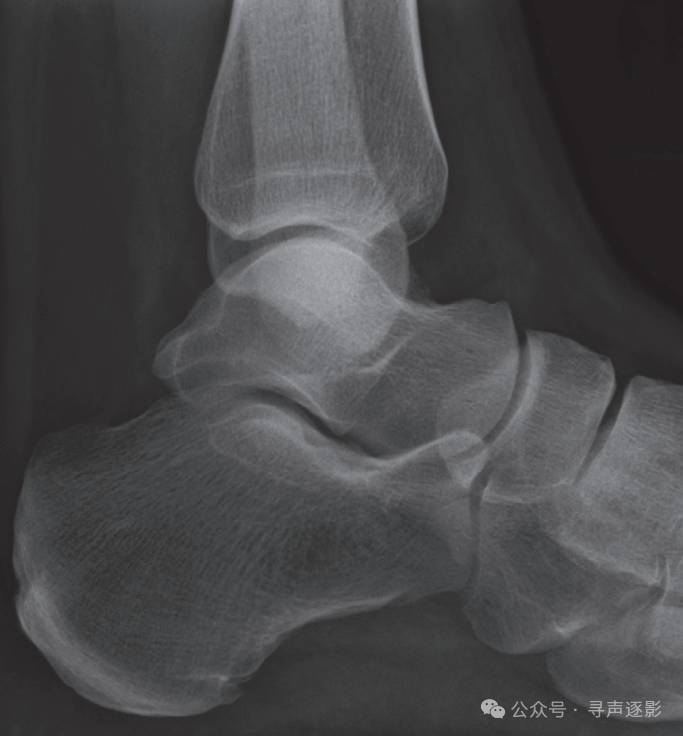

正常踝关节侧位片

【侧位】

□ 胫骨:皮质完整?关节面光滑?

□ 腓骨:注意斜行骨折线

□ 距骨颈:一条透亮线也可能坏死

□ 距舟关节:关节间隙清晰可见?

□ 跟骨:

• 有骨折线?

• Bohler角≥30°?

• 前突完整?

□ 第5跖骨基底:撕脱骨折最爱藏这儿